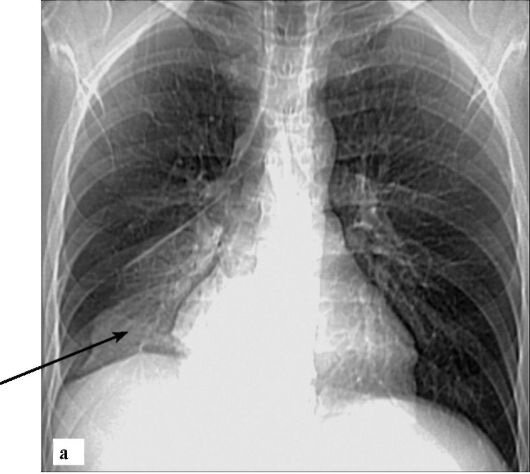

Правосторонняя нижнедолевая пневмония на рентгенограмме

При крупозной пневмонии выявляется снижение прозрачности лёгочной ткани, оно может быть тотальным (поражение всего лёгкого), субтотальным (поражение одной или нескольких долей), сегментарным, когда инфильтрация занимает 1 или несколько сегментов.

Для воспаления лёгких характерно усиление легочного рисунка, расширение корня легкого на стороне поражения. Возможно появление плеврального выпота (жидкости в плевральной полости).